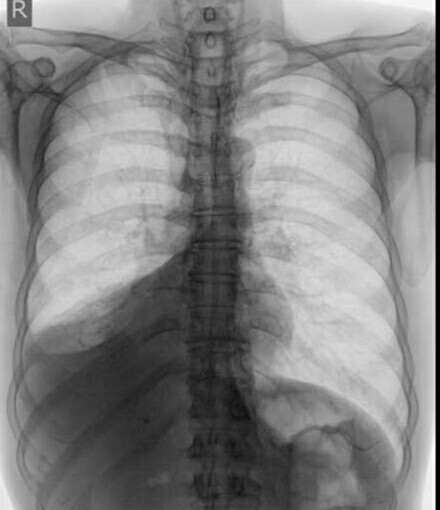

患者男,60岁,胸部不适1月余,吐浓黄色痰,无明显其他症状。胸部平片示:右下肺心脊柱旁心后区片状密度增高影,尖端指向肺门,右膈抬高,右肋膈角变钝,考虑:右肺下叶不张(原因?),右膈膨升,右侧胸膜炎,建议进一步CT检查。请大家谈谈每一叶肺不张的胸片表现。